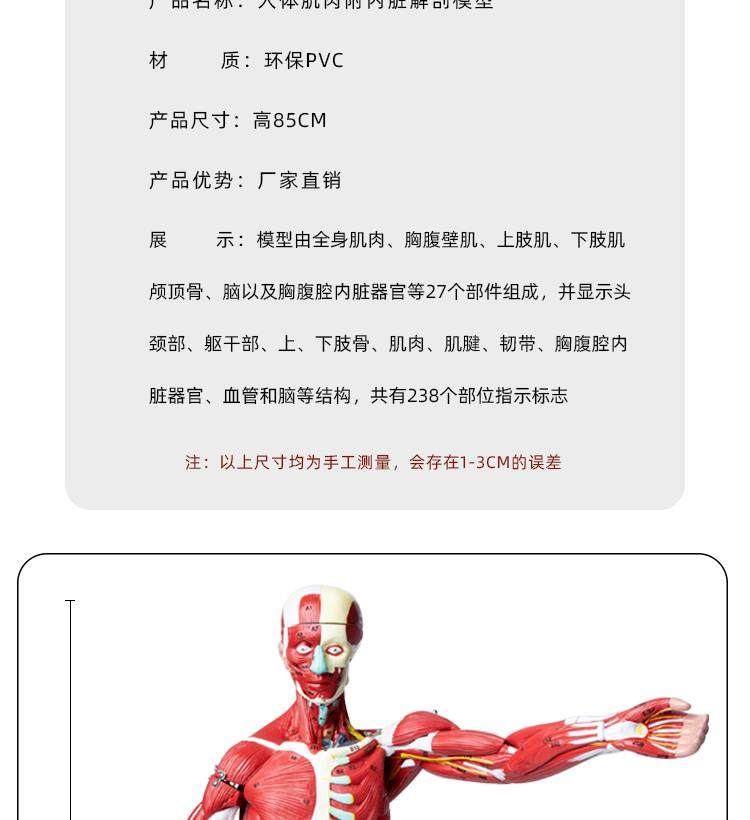

Human Body Muscle Internal Organ Disassembly Anatomy Structure Model Tissue Exercise Artificial Medical Teaching Aids

| Product Specifications | |

| Brand | No Brand (No Registered Trademark) |

| Model | 6622 |

| Applicable Age | 14 Years Old+ |

| Origin | Mainland China |

| Toy Type | Melissabow Toys |

| Applicable Gender | Universal |

| Color Classification | 85 Human Muscle Internal Organs Removable Organ,50cm Muscle Model |